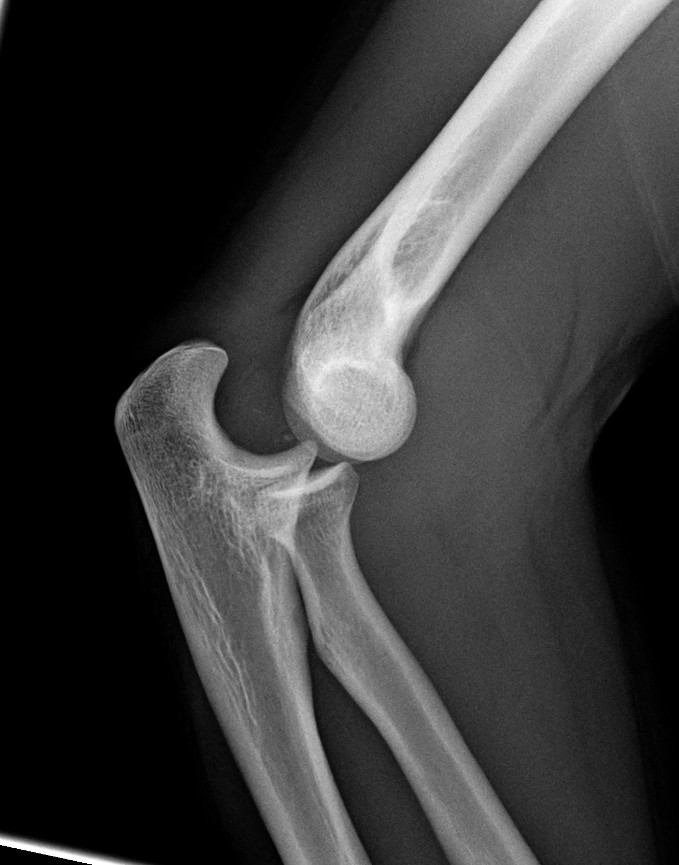

Luxación + fractura de cúpula radial: en estos casos se encuentra dislocado el codo y asociado una fractura de la cabeza de radio; debe primero reducir la luxación para determinar el tipo de tratamiento que se puede dar a la cúpula radial.

Síntesis de Cúpula radial: Las fracturas de la cúpula radial deben intentar ser reparadas para conservarla en su sitio y prevenir cualquier alteración de la función del codo o antebrazo, e incluso evitar dolor crónico en la muñeca. En ocasiones es necesario realizar síntesis o cirugía de reconstrucción de la cabeza radial como en esta imagen.

Artroplastia / Reemplazo articular de cúpula radial: En algunas lesiones, seleccionadas, donde la reconstrucción de la cúpula o cabeza de radio no es posible se puede colocar prótesis de la cabeza radial para preservar el espacio y limitar las secuelas en el resto del miembro superior.